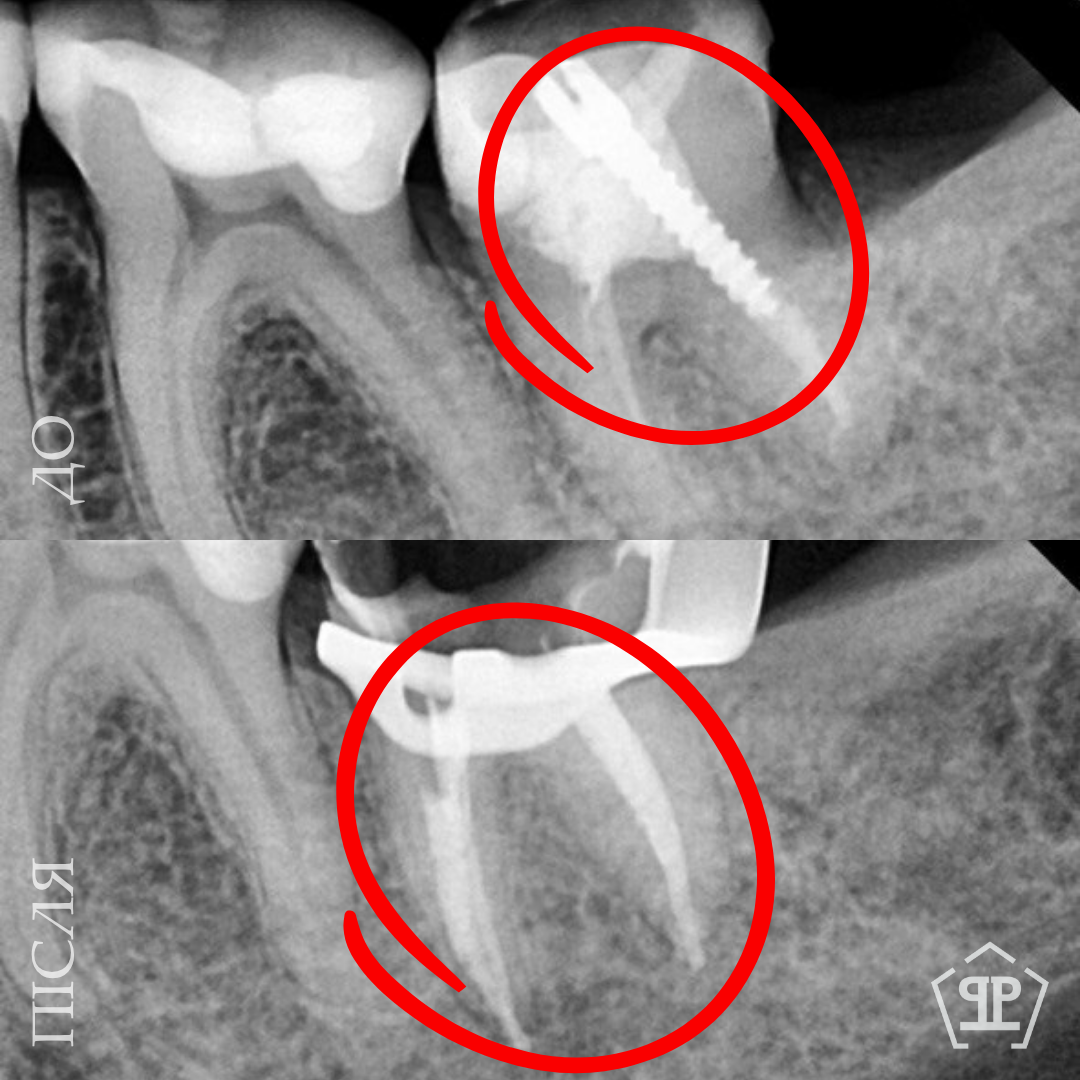

Во время диагностики обнаружен отлом фрагмента инструмента в корневом канале. Выполнено его безопасное извлечение, повторное перелечивание каналов, очистку и герметичное пломбирование.